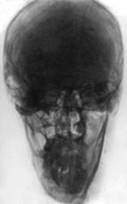

Рентгеновская картина черепа взрослого человека

Вид спереди.

1-крыша (свод) черепа;

2-лобная кость;

3-лобная пазуха;

4-ячейки решетчатой кости;

5-костная перегородка полости носа;

6-передняя носовая ость;

7-межверхнечелюстной шов;

8-нижняя челюсть;

9-подбородочный выступ;

10-полость носа;

11-верхнечелюстная пазуха;

12-сосцевидный отросток;

13-глазница.